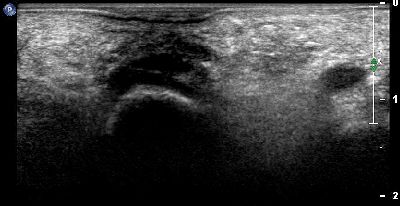

Calcificazione intra articolare (img. 01) Calcificazione intra articolare 01

Calcificazione intra articolare (img. 02) Calcificazione intra articolare 02

Calcificazione intra articolare (img. 03) Calcificazione intra articolare 03